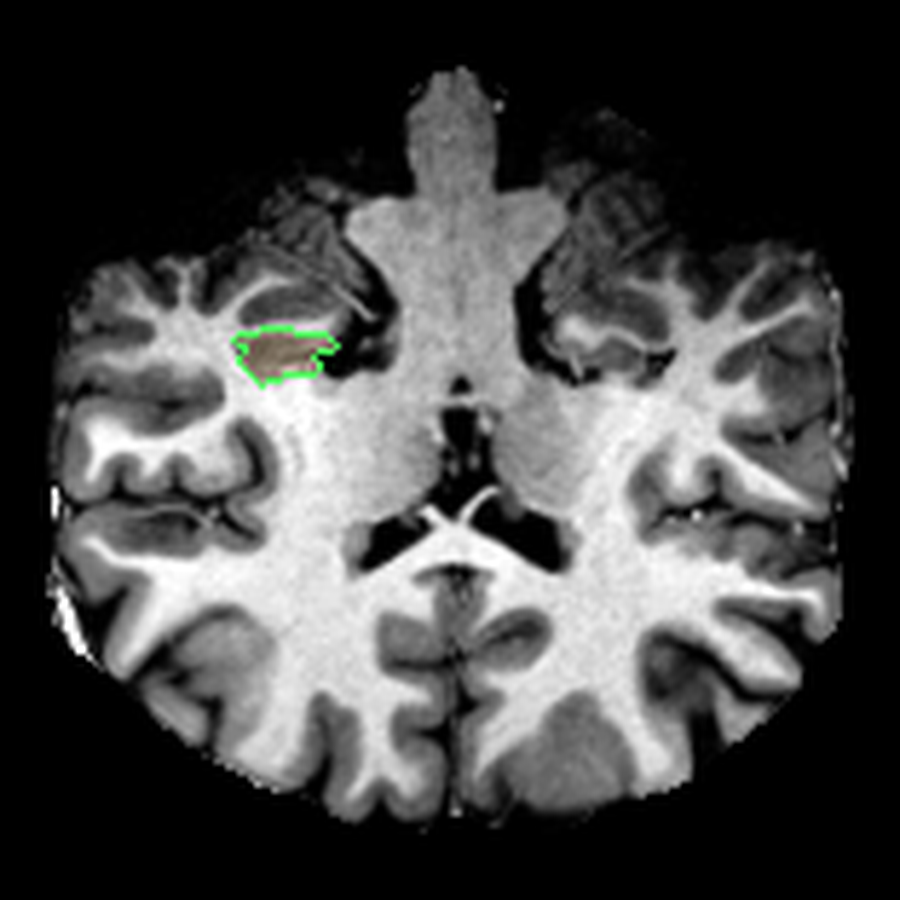

What I liked about having this data was that it changed how I interacted with the scan. Instead of staring at individual slices and guessing at the composition, I could start isolating specific parts of the brain.

The visualisations above show how little differentiation some brain regions have from their surroundings - I knew roughly where the thalamus was in the brain, but would never have been able to point it out on the MRI. At this stage, FreeSurfer plus some code had given me a perspective that would have been impossible for me to achieve myself.